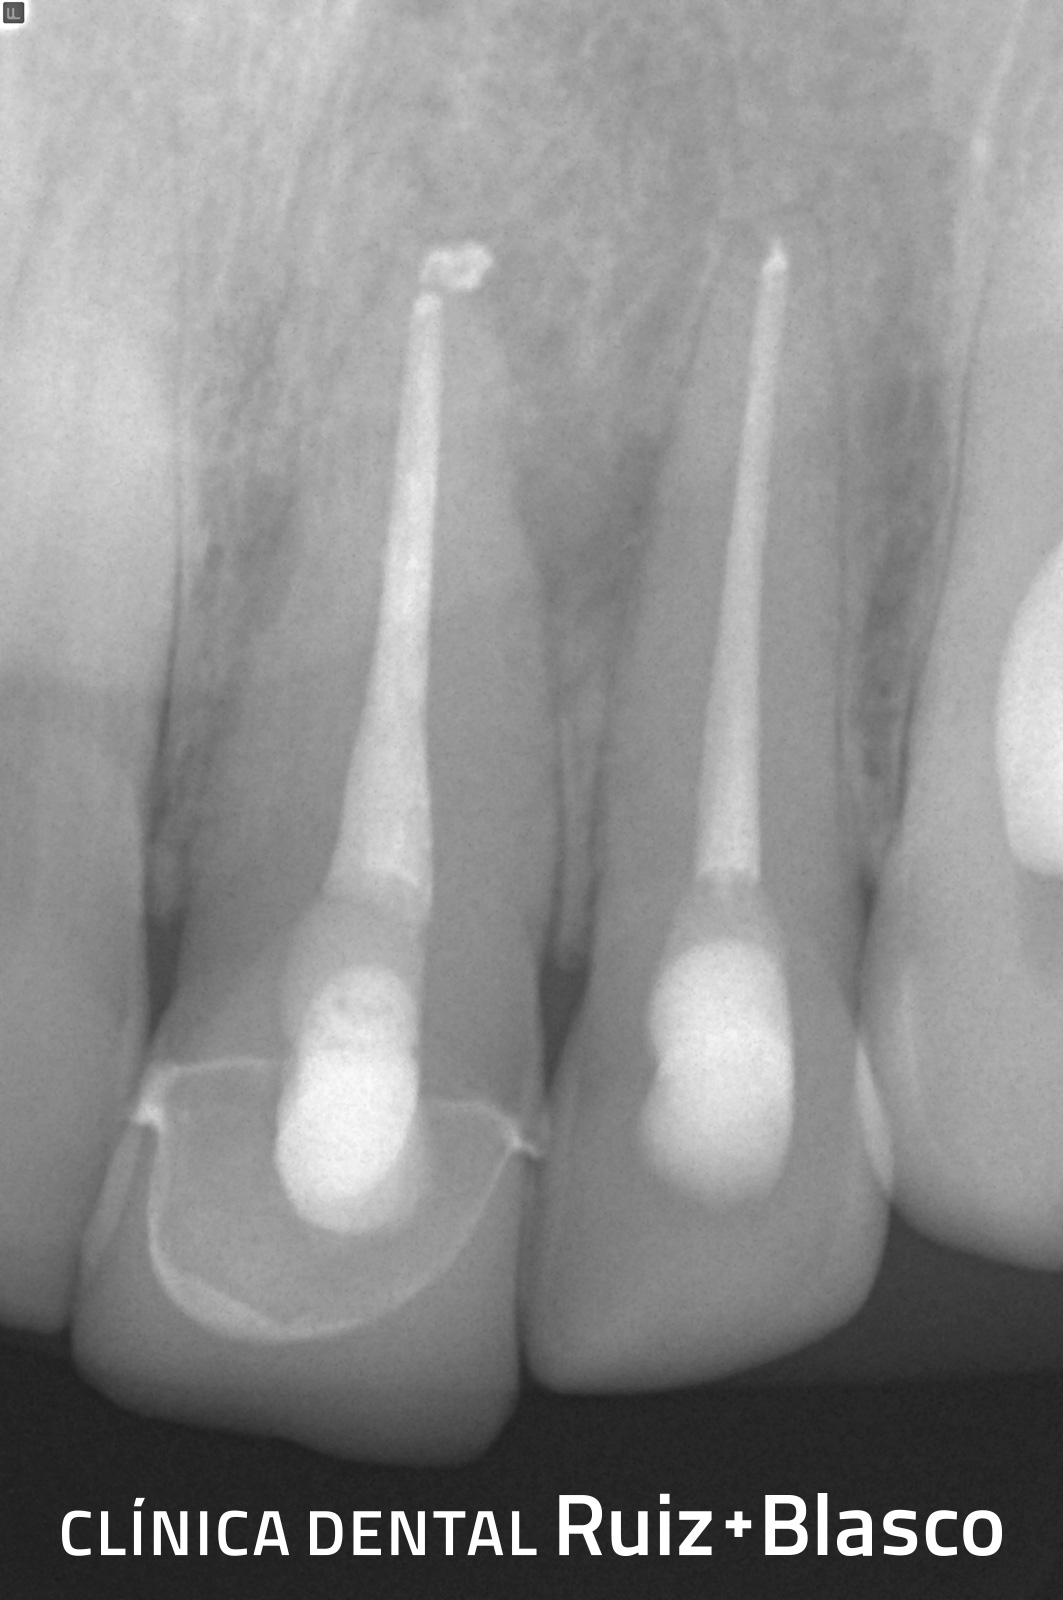

Nos encontramos con un paciente al que, tras la exploración rutinaria, se le descubrió una necrosis de los incisivos centrales y laterales. Esta necrosis –debido a una infección de la pulpa dental– había provocado otra infección en los tejidos periapicales (alrededor del ápice de las raíces). Se le realizó el tratamiento de conductos y, 6 meses más tarde, podemos observar la desaparición del área de infección periapical.